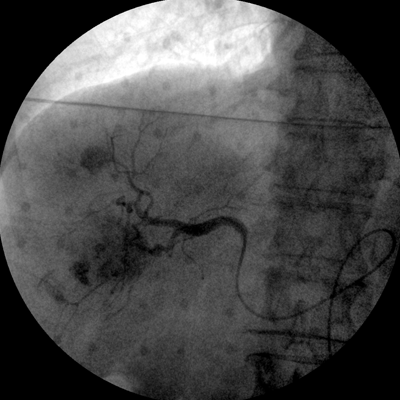

數(shù)字高清影像  助力臨床診斷

專業(yè)的圖像處理系統(tǒng),為您提供高分辨率、高灰階圖像。

Clinical picture

臨床圖片